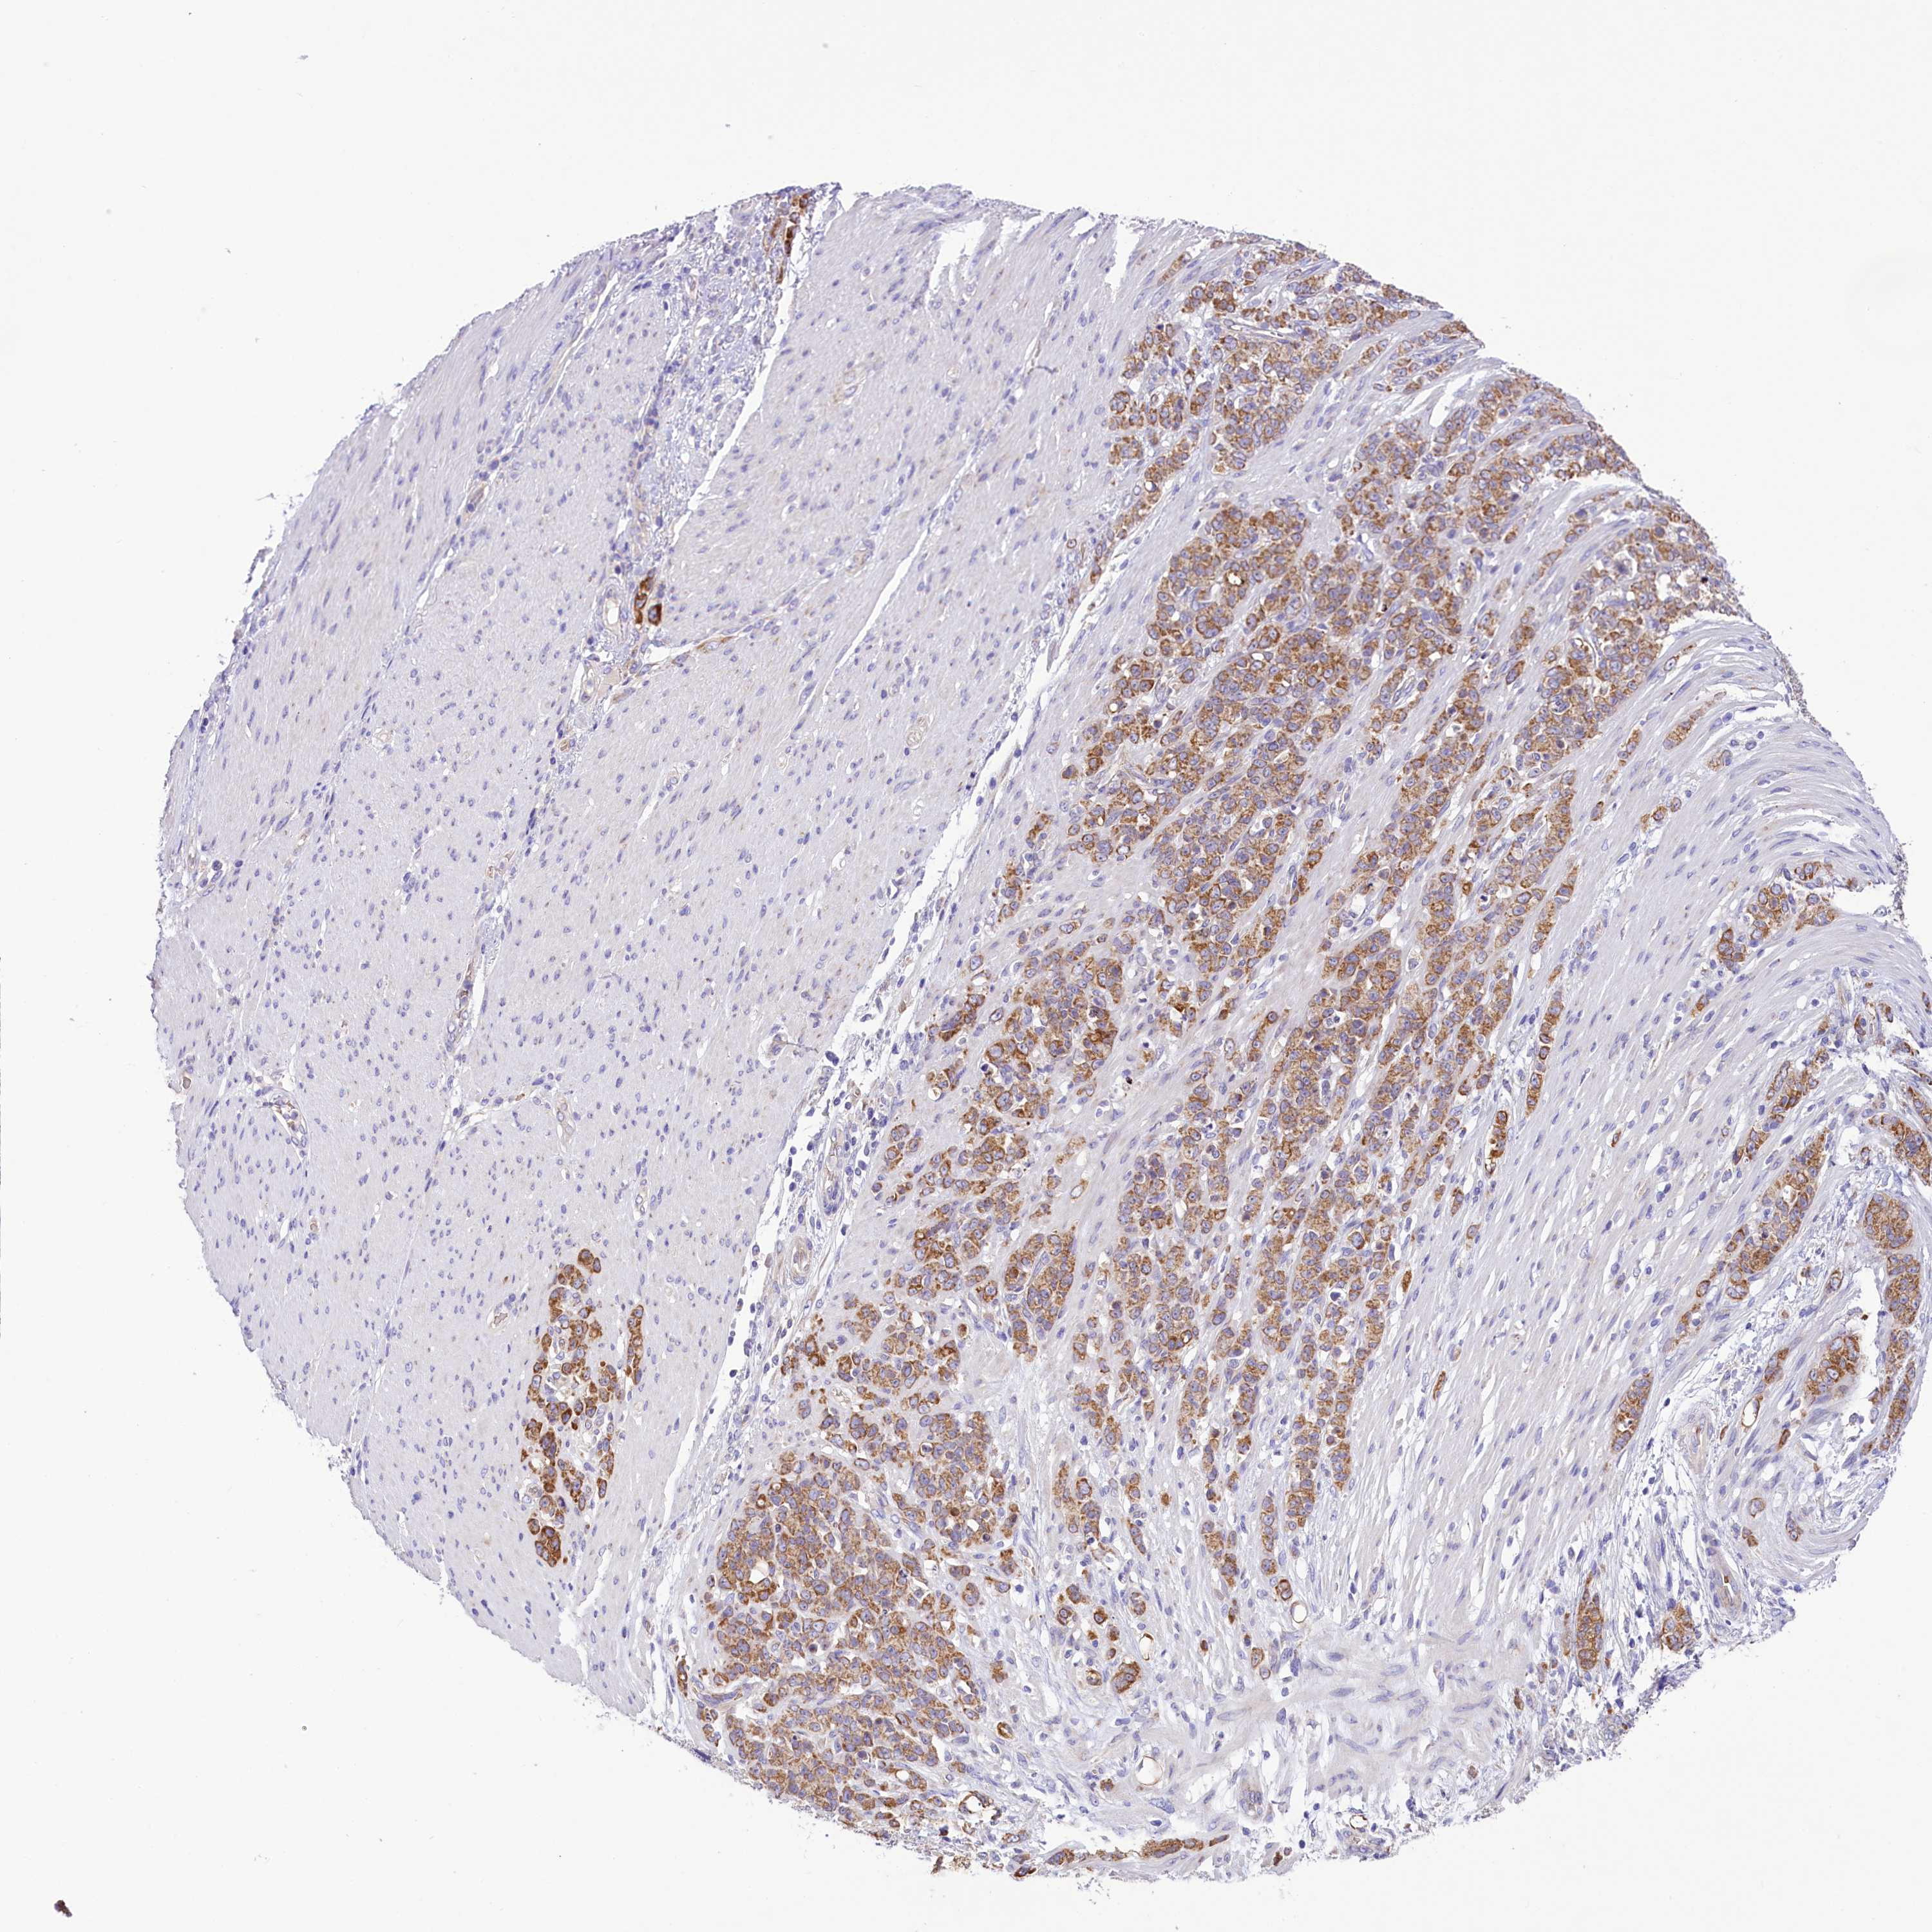

STOMACH CANCER - Protein expressioni

A mouse-over function shows sample information and annotation data. Click on an image to view it in a full screen mode. Samples can be filtered based on level of antibody staining by selecting one or several of the following categories: high, medium, low and not detected. The assay and annotation is described here.

Note that samples used for immunohistochemistry by the Human Protein Atlas do not correspond to samples in the TCGA dataset.

Antibody stainingi

Antibody staining in the annotated cell types in the current human tissue is reported as not detected, low, medium, or high, based on conventional immunohistochemistry profiling in selected tissues. This score is based on the combination of the staining intensity and fraction of stained cells.

Each image is clickable and will lead to virtual microscopy that enables deeper exploration of all samples and also displays staining intensity scores, fraction scores and subcellular localization as well as patient and tissue information for each sample.

Antibody HPA039306

Antibody HPA039673

Staining

High

Medium

Low

Not detected

Intensity

Strong

Moderate

Weak

Negative

Quantity

>75%

75%-25%

<25%

None

Location

Nuclear

Cytoplasmic/membranous

Cytoplasmic/membranous,nuclear

Adenocarcinoma, NOS